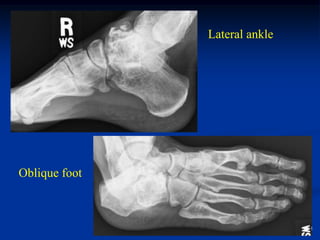

Case #625.1                 Multiple hereditary exostoses

50 yr old female with short stature and R hip pain for years

AP and lateral of right hip

AP and lat tibia

Proximal humeral x-rays

AP and lateral of femur

Lateral ankle

Oblique foot